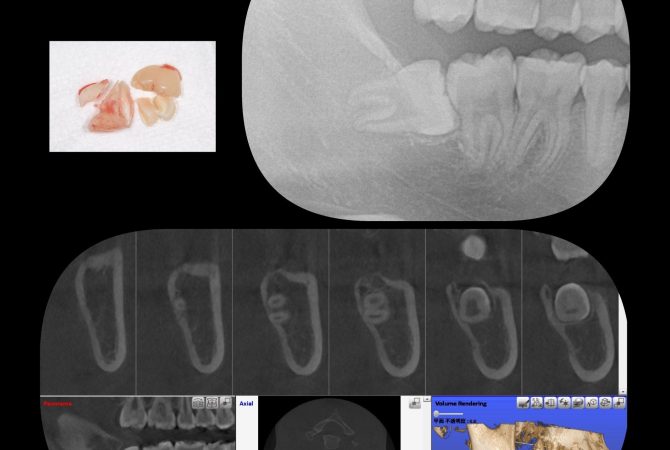

2025.11.15 イベントその他 5歳児健康診査へ行ってきました♪ 詳しく見る 2025.11.14 症例 EMS社エアフローを使用した定期検診症例 詳しく見る 2025.11.12 症例 横向き親知らずの抜歯症例 詳しく見る 2025.10.27 インプラント学び インプラントのための骨造成セミナーを受講 詳しく見る 2025.10.26 イベント院内のこと ハロウィンWeek★キッズイベント開催中 詳しく見る 2025.10.21 学び 博多で歯科麻酔セミナーを受講 詳しく見る 2025.10.19 症例 拡大床と3DLによる小児矯正症例 詳しく見る 2025.10.14 症例 横向き親知らずの抜歯症例 詳しく見る 2025.10.5 治療院内のこと 最新の電動麻酔器を導入♪ 詳しく見る 1 / 29 ページ23…29次へ »